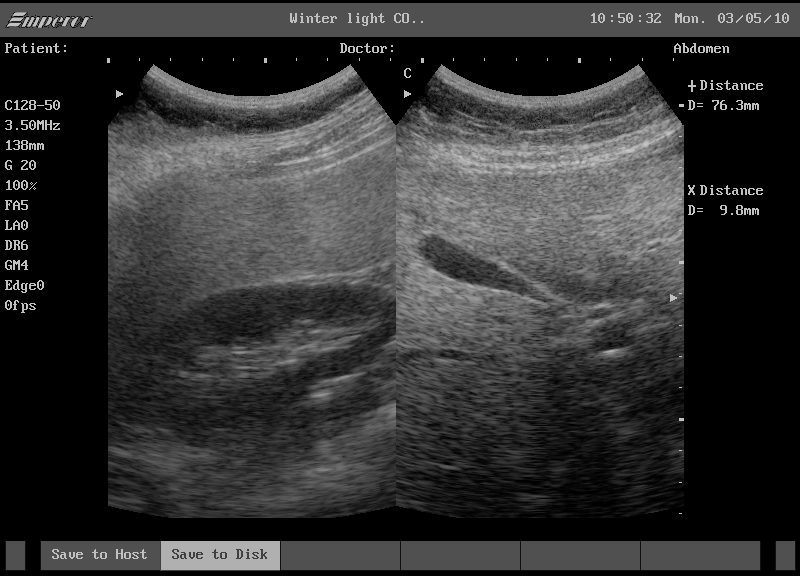

복부 초음파(Abdominal Ultrasonography)는 인체에 무해한 초음파를 이용해 복강 내 장기들을 영상으로 확인하는 비침습적 진단 방법입니다. 흔히 건강검진에서 기본적으로 포함되며, 간, 담낭, 신장, 췌장, 비장 등 주요 장기의 구조적 이상을 빠르고 안전하게 확인할 수 있습니다. 검사 시간은 10~20분 이내로 비교적 짧고, 방사선 노출이 없어 반복 검사도 안전하게 진행할 수 있습니다.

이러한 장기들의 모양, 크기, 내부 구조, 혹은 결석 및 종괴 여부 등을 시각적으로 확인할 수 있어 질환의 조기 진단과 추적관찰에 매우 유용합니다.

복부 초음파로 알 수 있는 질환